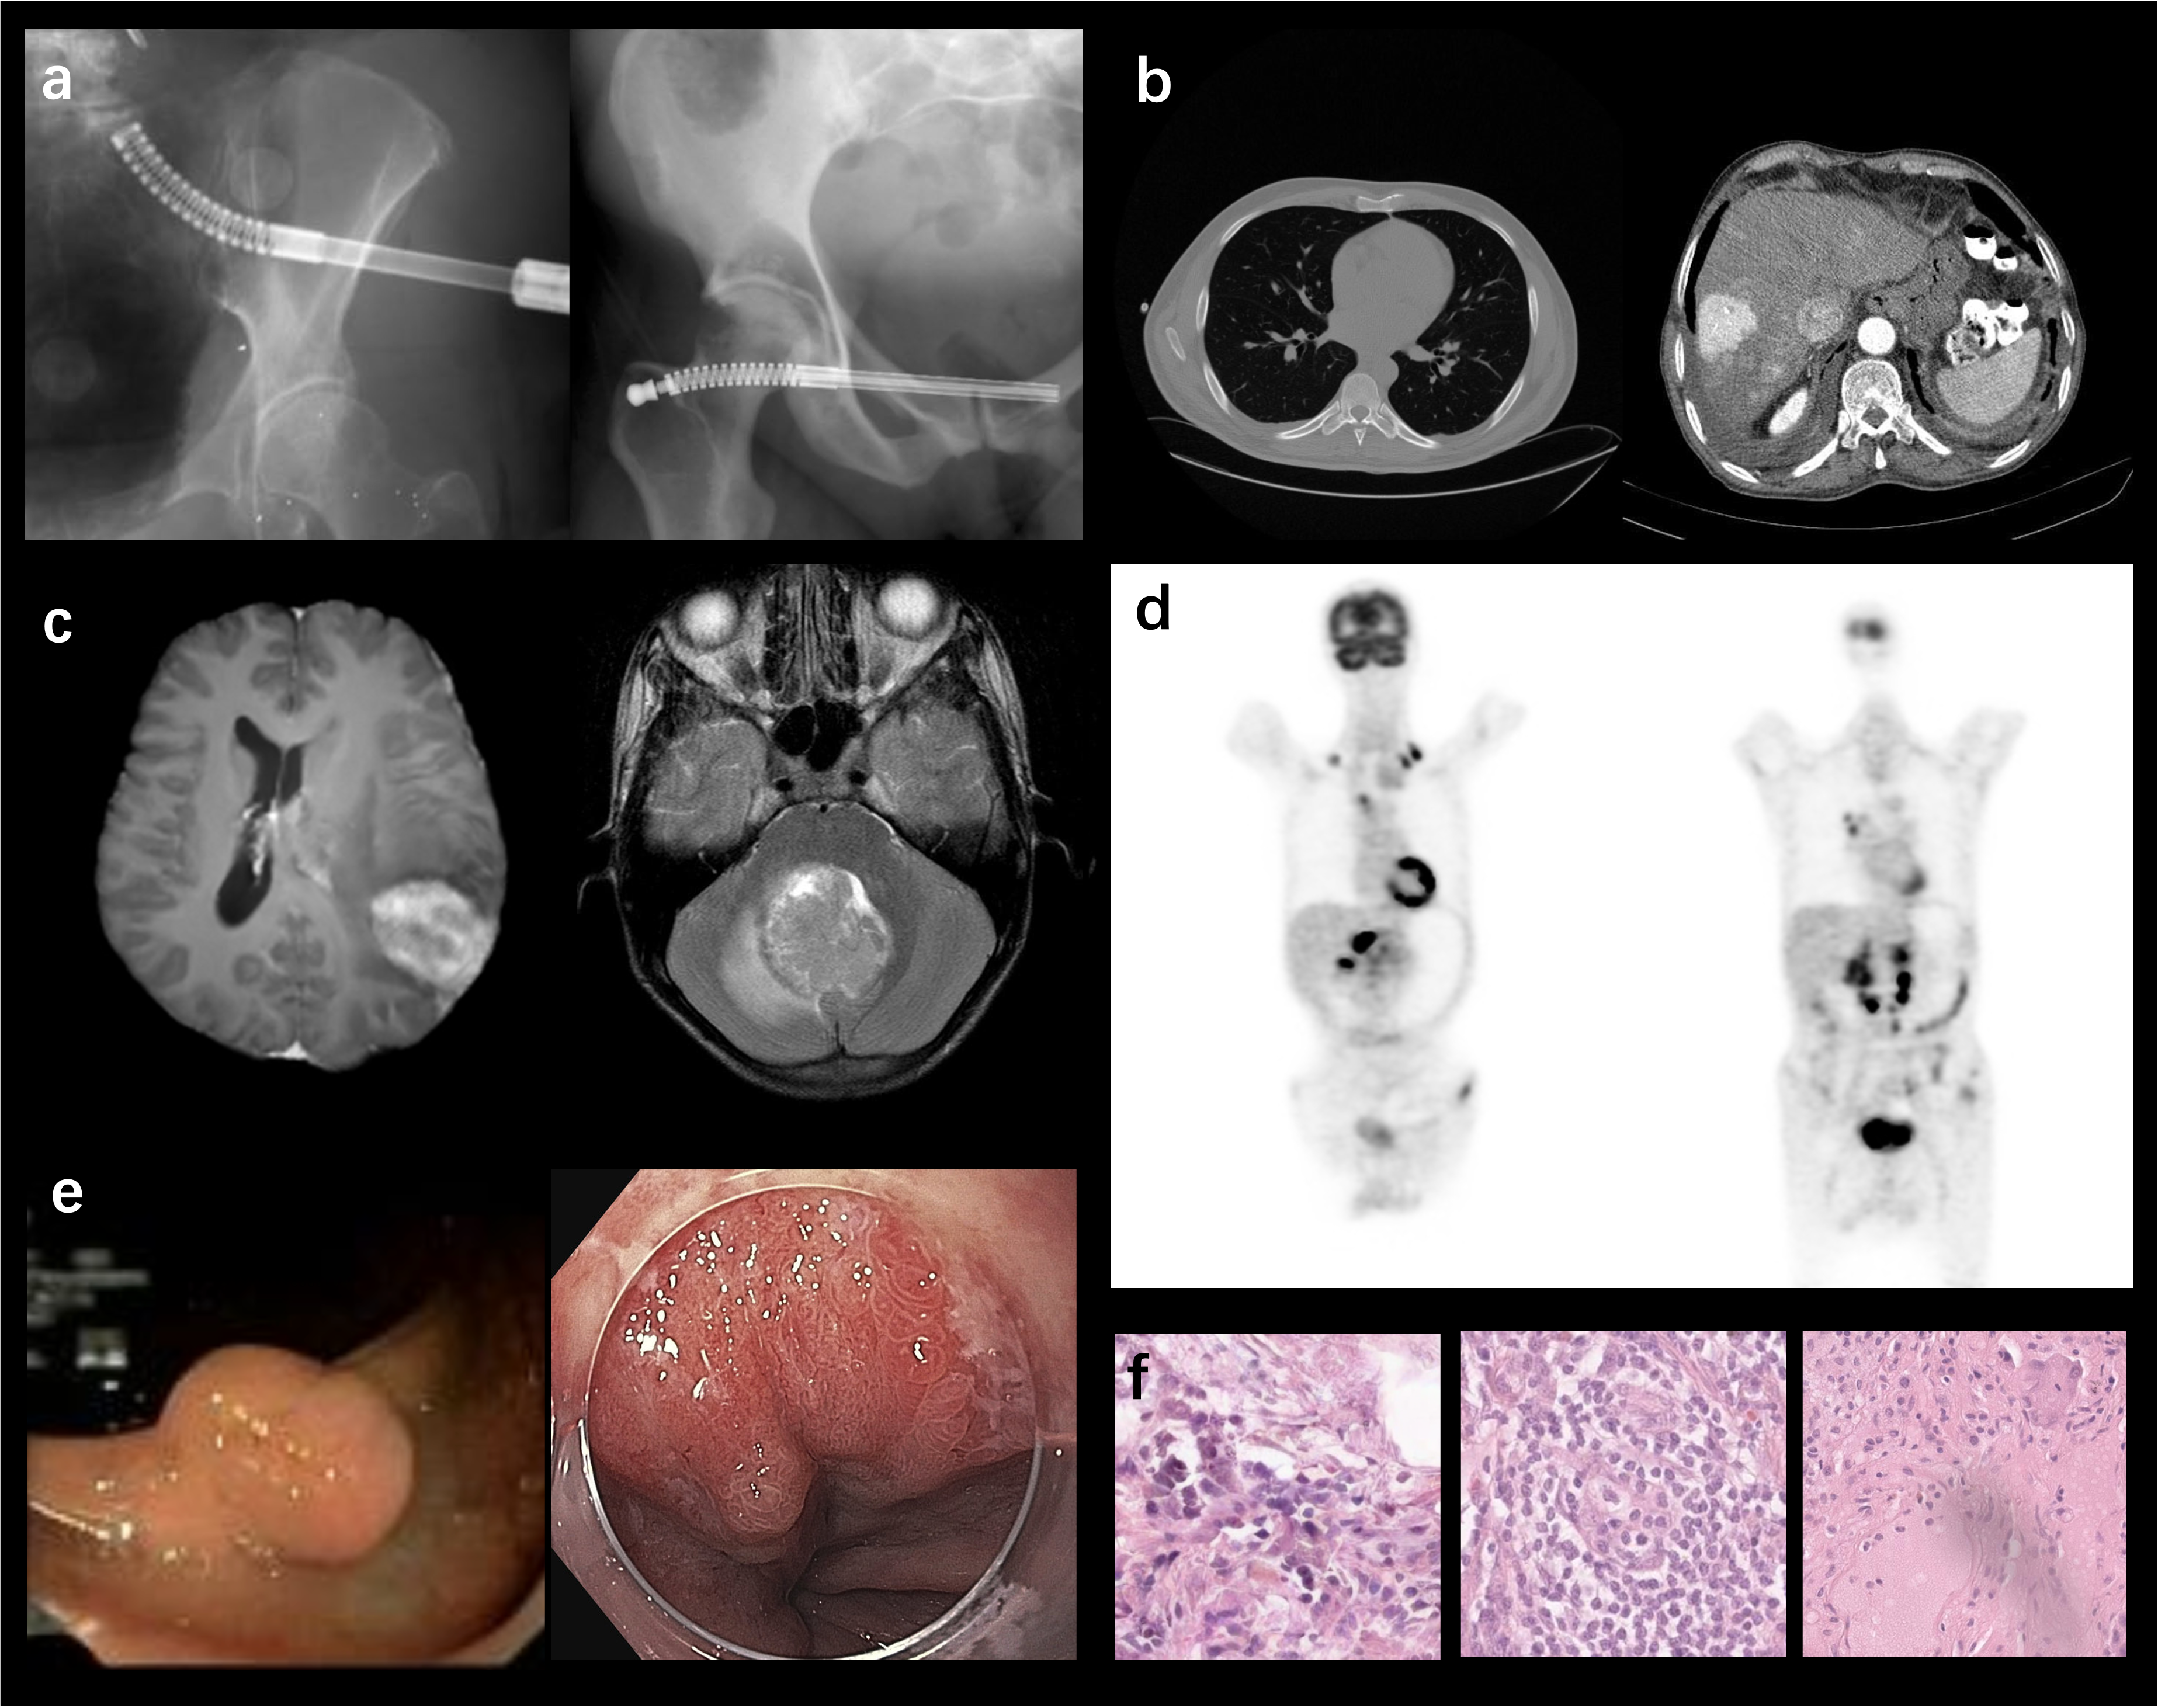

Refer to caption

Figure 1: Can you distinguish synthetic data from real data in different modalities? (a) X-ray image examples gao2023synthetic . (b) CT image examples hamamci2023generatect . (c) MR image examples park2021generative . (d) PET image example. (e) Endoscopy image example li2024endora . (f) Histopathology image example aversa2024diffinfinite .